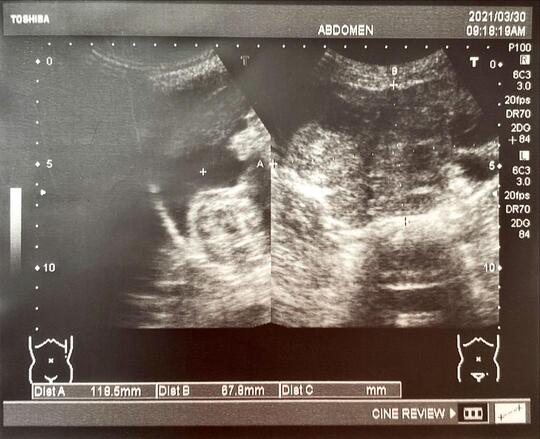

超音波影像如圖,腹腔有明顯腹水,下腹有明顯腫瘤,

轉診至醫院婦產科進一步檢查,

確診為卵巢癌,目前已接受手術及化療,後續於醫院固定追蹤。